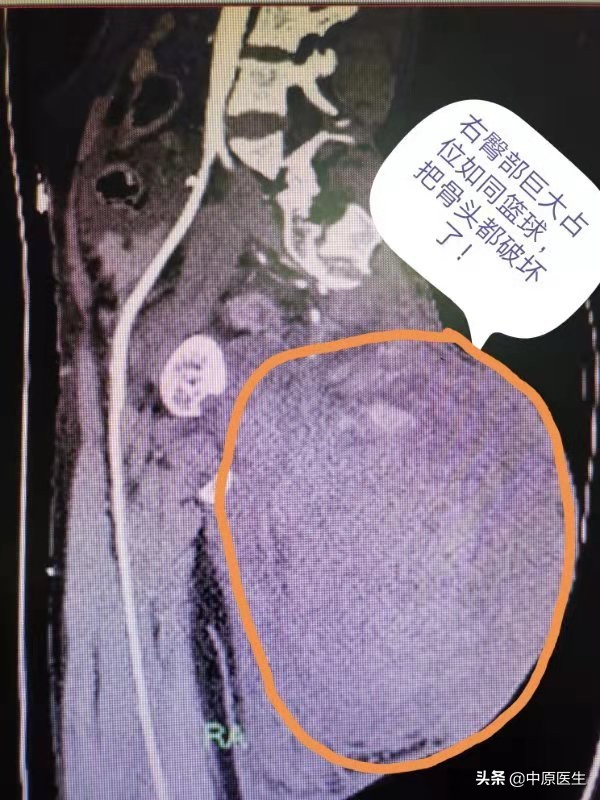

据曹广劭介绍,女子50岁左右,目前在郑州装修公司打工,右侧臀部这个肿瘤已经有近30年历史,30年前患者就发现了,当时只有鸡蛋大小。

肿瘤就这样越长越大,由鸡蛋大小长到拳头大小,再到足球大小,穿衣服已经能明显看出来了,这还不是最要紧的,关键是坐下来或平躺时这么大的肿瘤就碍事了,一会就酸痛不适,但肿瘤是几十年慢慢长起来的,病人整天忙于生计,也就适应了肿瘤的存在。

7月28日下午,患者与丈夫在郑州东区正在做装修工作时,突发剧痛,屁股上的肿瘤也跟吹气球似的瞬间增大,由足球大小变成了篮球大小,紧接着就是头晕、心慌,不能站立也不能坐下,只能痛苦的趴在地上。

急诊科医生看到这种情况考虑是肿瘤内部出血了,把肿瘤吹气球似的撑起来了,张力非常大,随时都有爆掉的可能似的,病人只能痛苦的趴在那,血压扑簌簌的下降至70/40mmHg,急查血常规提示血红蛋白已经由正常人的120g/L左右降低至43g/L,再晚来一会估计就有生命危险了。

半夜急诊CT出来一看,证实肿瘤就是出血了,肿瘤早把附近骨头破坏了,真佩服这个母亲的忍受力!与家属充分沟通后,等待二女儿过来后行微创介入栓塞。